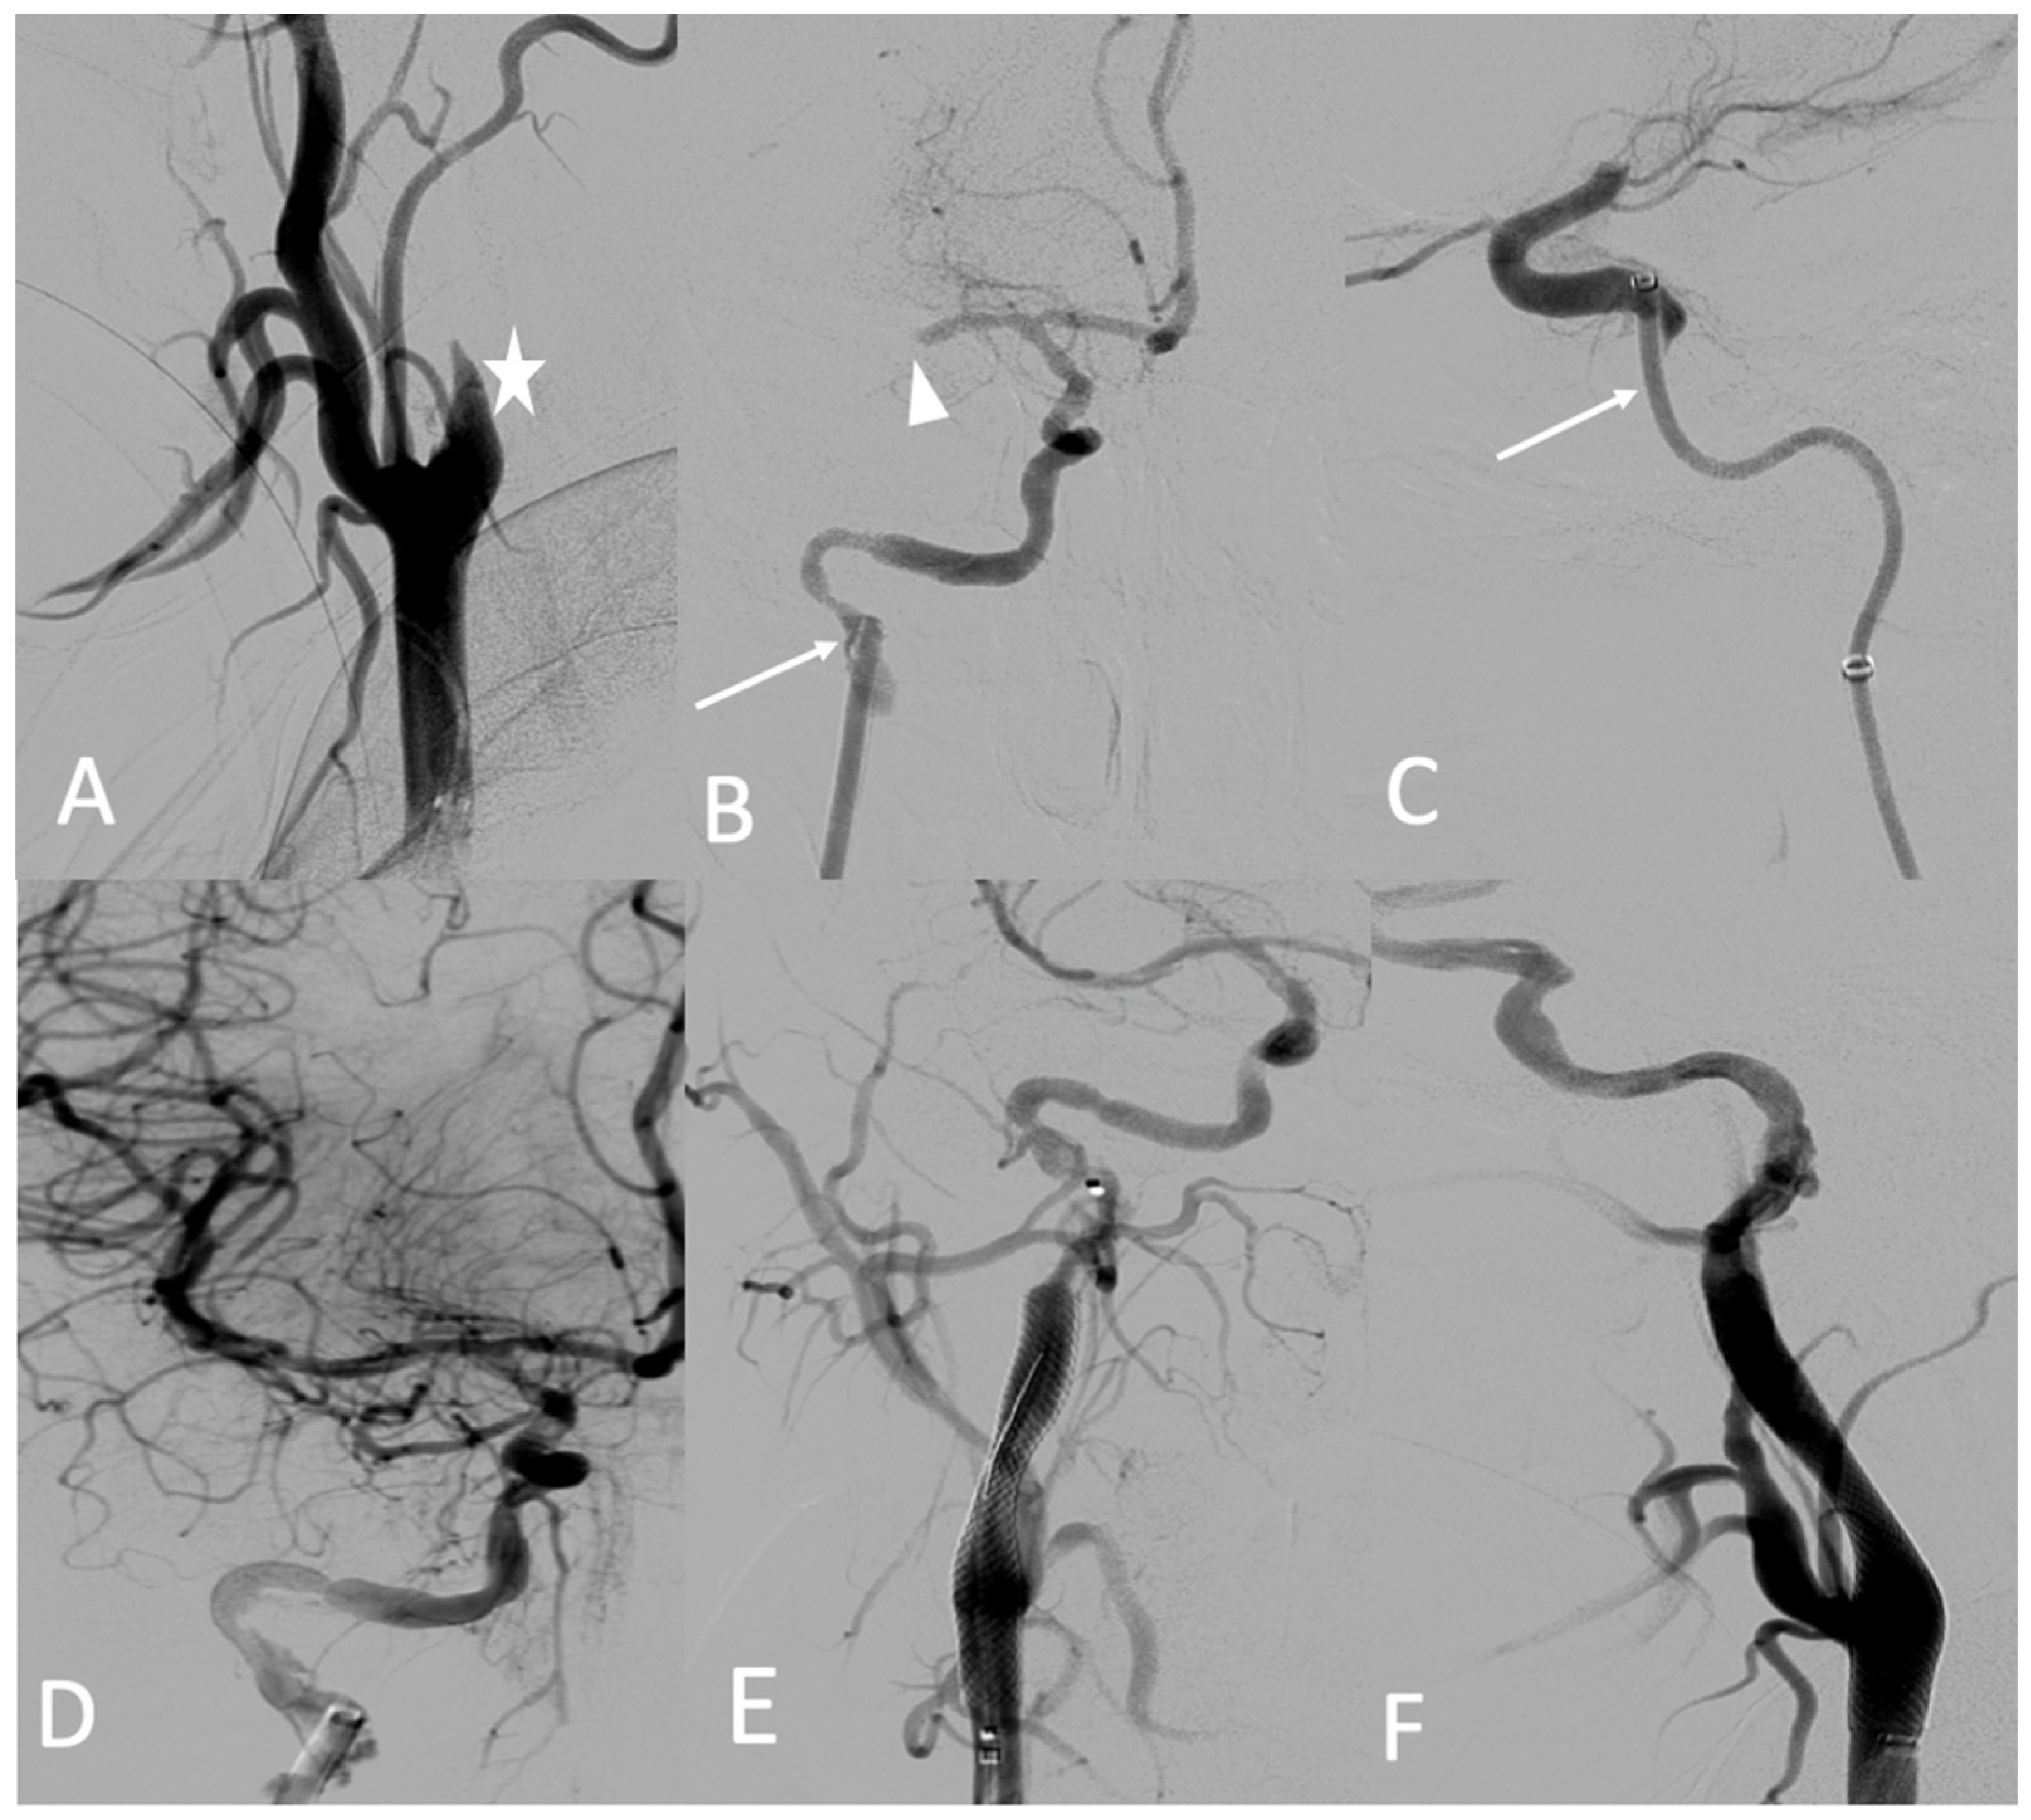

A 25-year-old male patient, with a familial history aortic rupture leading to the sudden death of his father in 1999, was referred to our hospital after the appearance of a left groin hematoma. An enhanced abdominal and pelvic CT scan revealed an aneurysm of the splenic artery measuring 30 × 25 mm and a recent dissection of the left common iliac artery, with a maximum iliac diameter of 12 mm (Figure 3A,B). In his medical history, he complained of abdominal pain within the left hypochondrium for the past 8 months following physical exercise. After a multidisciplinary evaluation, we first decided to embolize the splenic aneurysm using coils to prevent the risk of rupture. Under general anesthesia, a 6 F introducer was inserted into the left humeral artery using the Seldinger technique. Two-dimensional/three-dimensional fusion with preoperative CT angiography was performed to guide the catheter and microcatheter for the more rapid catheterization of the aneurysm and to decrease the radiation exposure (Figure 3C). We catheterized the celiac trunk artery using a 6 F ENVOY catheter (Codman-USA) and then catheterized the aneurysm using a Progreat 2.8 F microcatheter (Terumo-Tokyo, Japan). We started to exclude the outflow of the aneurysm with several Ruby coils (Penumbra-Alameda, CA, USA). We then filled the aneurysm with multiple coils starting with a 3D Ruby standard coil of 34 mm diameter and after decreasing the diameter of the coils using interlock detachable coils (IDCs, Boston Scientific, Marlborough, MA, USA), Nester coils (COOK 6 USA), and packing coils (Penumbra-Alameda, CA, USA), and we occluded the aneurysm inflow using Ruby standard coils (Penumbra-Alameda, CA, USA) (Figure 3D).

Figure 3.

(A,B) Abdominal CT angiogram with 3D image and arteriography with image fusion (C,D) showing the aneurysm in the splenic artery (arrows). We marked the proximal and distal extremities of the neck of the aneurysm (head arrow), and then we started the embolization using multiple coils after, within, and before the aneurysm.

Successive CT scan follow-up revealed rapid aneurysmal growth of his left common iliac artery with a 12 mm increase in diameter within one week. The patient complained of left groin pain. A hybrid surgical treatment of left iliofemoral bypass and endovascular exclusion of the internal iliac artery was selected (Figure 4).

Figure 4.

(A) Abdominal CT angiogram with 3D image showing the dissection of the left common iliac artery (arrow); (B) arteriography shows the left iliofemoral bypass (star) and dissection of the left common iliac artery (arrow); (C) occlusion of the left internal and external iliac arteries by coils and then a plug (head arrow); (D) arteriography final shows the permeability of left iliofemoral bypass (star).

During the iliofemoral bypass, a 6 Fr introducer was inserted into the left femoral artery. The left internal iliac artery was catheterized using both a 4 F cobra catheter (COOK-MEDICAL) and a Progreat 2.7 F catheter (Terumo-Tokyo, Japan). The internal iliac artery trunk was occluded using 6 × 60 POD coils (Penumbra-Alameda, CA, USA). Then, the common internal iliac artery was occluded using second-generation 10 mm Amplatzer vascular plugs and several coils (ABBOTT). The external iliac artery was occluded by several Amplatzer Plugs (ABBOTT). One week after the intervention, he complained of acute epigastric pain and presented with hemorrhagic shock. An enhanced abdominal and pelvic CT scan showed hemoperitoneum with aneurismal rupture of the left hepatic artery and an aneurysm of the celiac trunk and common hepatic artery (Figure 5). The patient was referred in extreme emergency to the interventional radiologist. A 6 F femoral access was performed to access the celiac trunk using the 6 F RDC catheter (Cordis-Santa Clara, CA, USA). Then, the left hepatic artery aneurysm was catheterized using a Progreat 2.7 F microcatheter (Terumo-Tokyo, Japan). The rupture of the left hepatic artery was confirmed on digital subtraction angiography (DSA), and the vessel was occluded using cyanoacrylate glue and multiple coils. DSA of the celiac trunk revealed an aneurismal evolution of the celiac trunk and the common hepatic artery with an occlusion of the common hepatic artery before the gastroduodenal artery. The common hepatic artery and celiac trunk were occluded using ethylene vinyl alcohol copolymer (Onyx, ev3, USA), several interlocking coils, and IDS (Boston Scientific, Marlborough, MA, USA) (Figure 5) without any complications during the procedure.

Figure 5.

(A,B) Axial and coronal abdominal CT images pertaining to the arterial phase show the aneurysm in the left hepatic artery (arrows) with perihepatic hematoma; (C) one coil was inserted in the aneurysm (star), and then glue and multiple coils were introduced into the common hepatic artery (arrowhead).